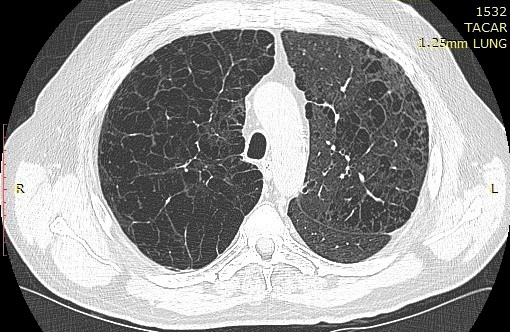

Presencia de enfisema por tomografía computada con espirometría normal